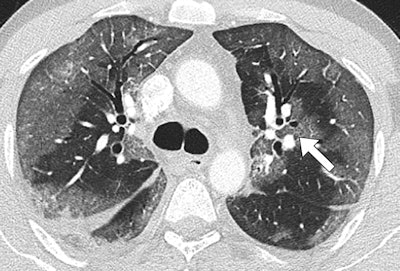

44-year-old man with MERS had no prior health problems. CT was performed one day after admission and nine days after symptom onset. The patient died in the intensive care unit. Upper-lung CT image shows large areas of bilateral subpleural ground-glass opacities. All images republished with permission of the American Roentgen Ray Society.

Midlung CT image shows that ground-glass opacities have peribronchovascular distribution (arrow).